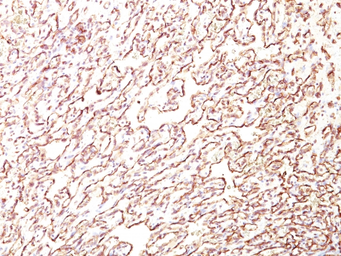

IHC-P analysis of human angiosarcoma tissue using GTX34978 PODXL antibody [4F10].